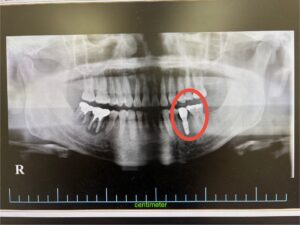

左下奥歯から1つ手前の歯が破折し、腫れや違和感が続いていたため、抜歯のうえインプラント治療をご希望されました。

破折歯を抜歯後、抜歯窩が完全に治癒するまで十分な期間を置き、その後インプラントを埋入しました。